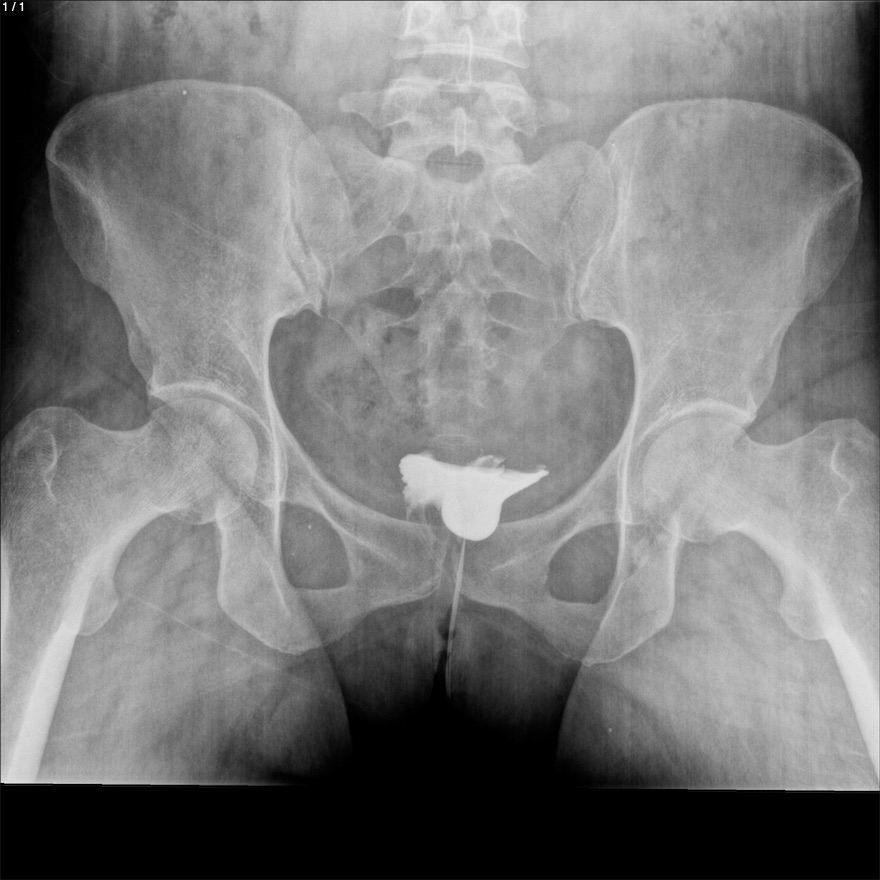

Blanca Flor Alvarez Marroquin - Unnamed